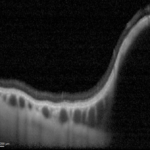

Varice della vena vorticosa: meno dell’1% fra gli pseudomelanomi